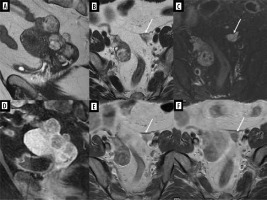

A 14-year-old patient had a lump in her right hand for 7 months, between the first and second metacarpal bones, which was initially assessed as a ganglion. The lesion was finally resected, and histopathological results revealed embryonal partial alveolar RMS. The girl was transferred to our centre for qualification for treatment. In the meantime, she felt a lesion/lump in the right breast. US revealed a nodular lesion 28 × 15 × 28 mm at 12 o’clock with irregular outlines and heterogeneous echostructure (Figure 7), as well as one larger hypoechoic lymph node and several smaller ones in the right axilla.

Figure 7

Ultrasound of right breast metastasis in Patient no. 3. A) Axial and sagittal plane. B) Colour Doppler, axial plane